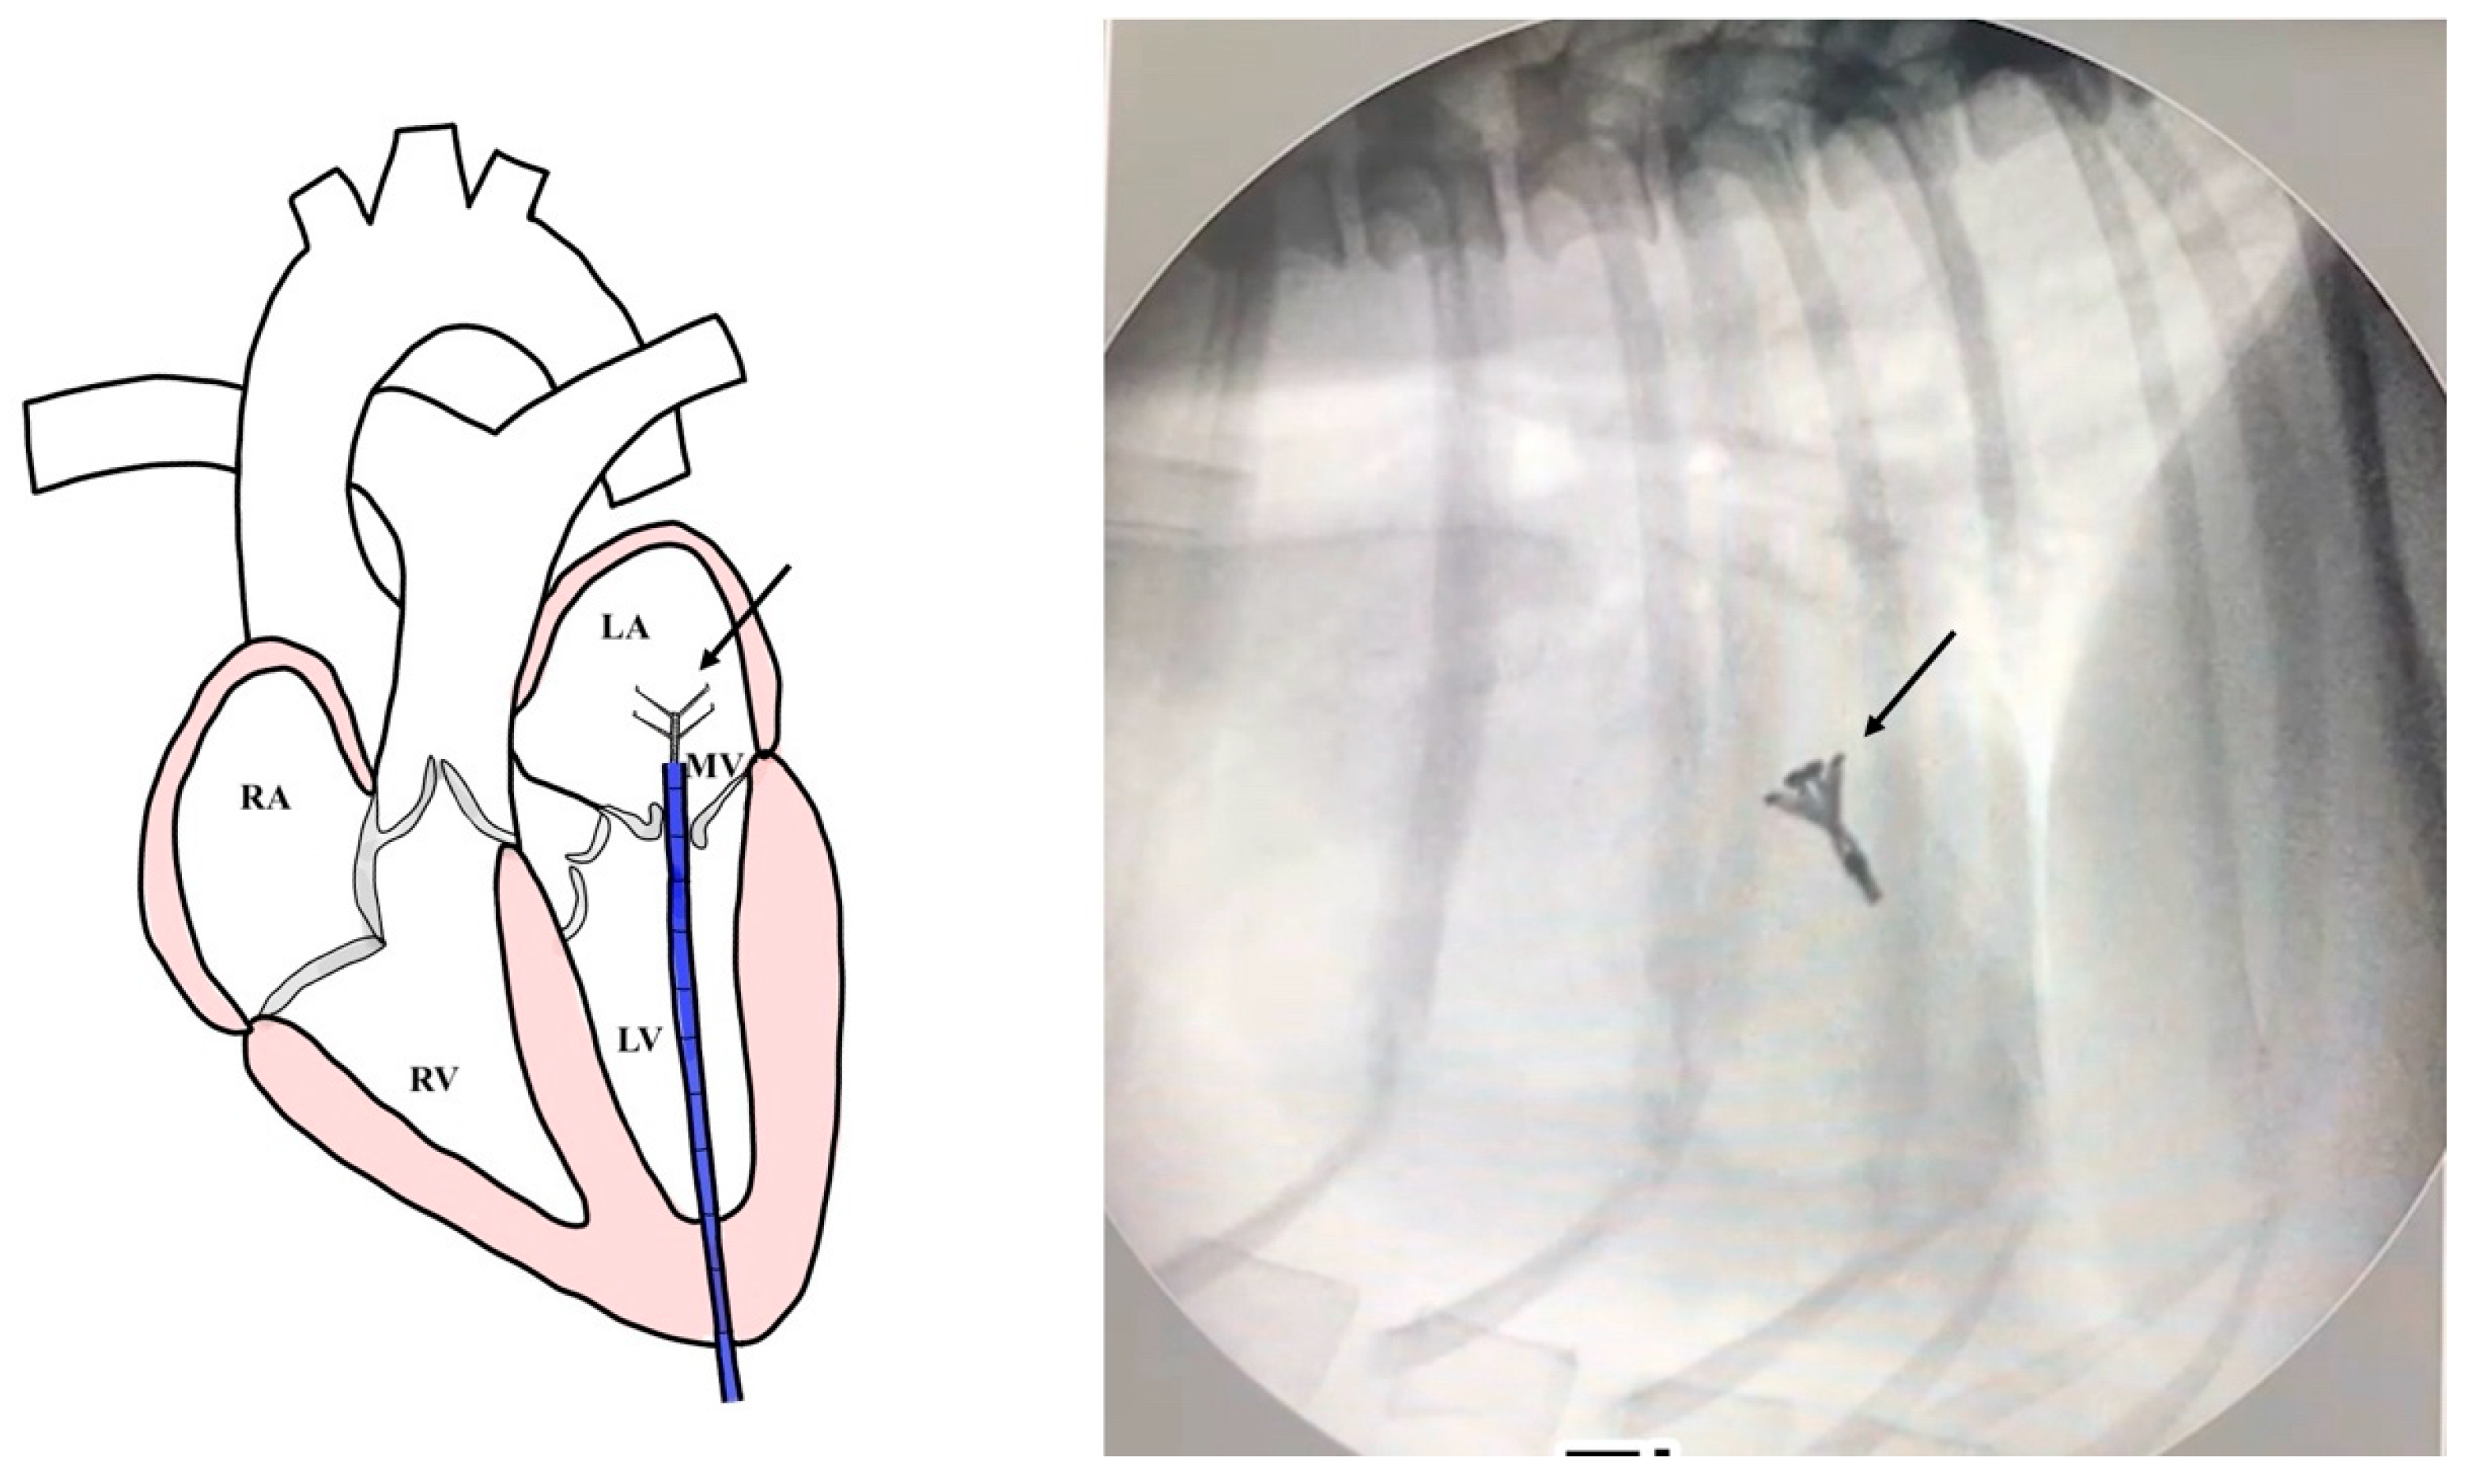

All dogs were assessed for a physical examination (inspection, palpation, percussion, and auscultation) for general health status. In this evaluation, mucous membranes, capillary refill time, rectal temperature, heart rate, heart sounds, pulse rate, and state of hydration were assessed. The dogs presented with a history of coughing, dyspnea, and exercise intolerance. Thoracic radiography revealed left heart enlargement (Figure 1). The mitral valve structure was evaluated by 3D transesophageal echocardiography, and a satisfactory clamp position was confirmed using fluoroscopy (GE, Boston, MA, USA). and 3D-TEE (Philips Medical Systems, Andover, MA, USA) as shown in Figure 2 and Figure 3.

2.5. Surgical Intervention

Figure 3. A V-clamp device placement (black arrow) with an introducer sheath of 14 mm was inserted into the left atrium (LA). A satisfactory clamp position was confirmed using fluoroscopy guidance. (RA = right atrium; RV = right ventricle; LV = left ventricle; MV = Mitral valve).